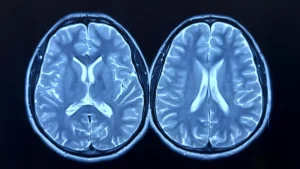

This extensive retrospective case-control investigation meticulously analyzed data extracted from comprehensive Danish national health registers, encompassing a...

A comprehensive investigation conducted in Sweden, drawing upon an extensive dataset of national health records, is prompting...